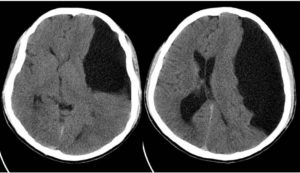

Нередко дополнительно проводится исследование в формате КТ. Нейровизуализация позволяет точно установить месторасположение кистозной полости, определить степень влияния на близлежащие участки здоровой ткани. Другие методы инструментального исследования:

Для точного выявления каналов сообщения между кистозной полостью и путями циркуляции ликвора используют методы: КТ- миелоцистернография и КТ- вентрикулография с введением контрастного вещества.

Картина арахноидальных изменений ликворокистозного характера в ходе исследований МР и КТ показывает наличие очагов с плотностью цереброспинальной жидкости, что подтверждает кистозную, неопухолевую природу образования.

- Компьютерная томография. Определяет положение и параметры опухоли.

- Магнитно-резонансная томография. МРТ картина арахноидальных изменений ликворокистозного характера отражает тип опухоли – злокачественная или доброкачественная.